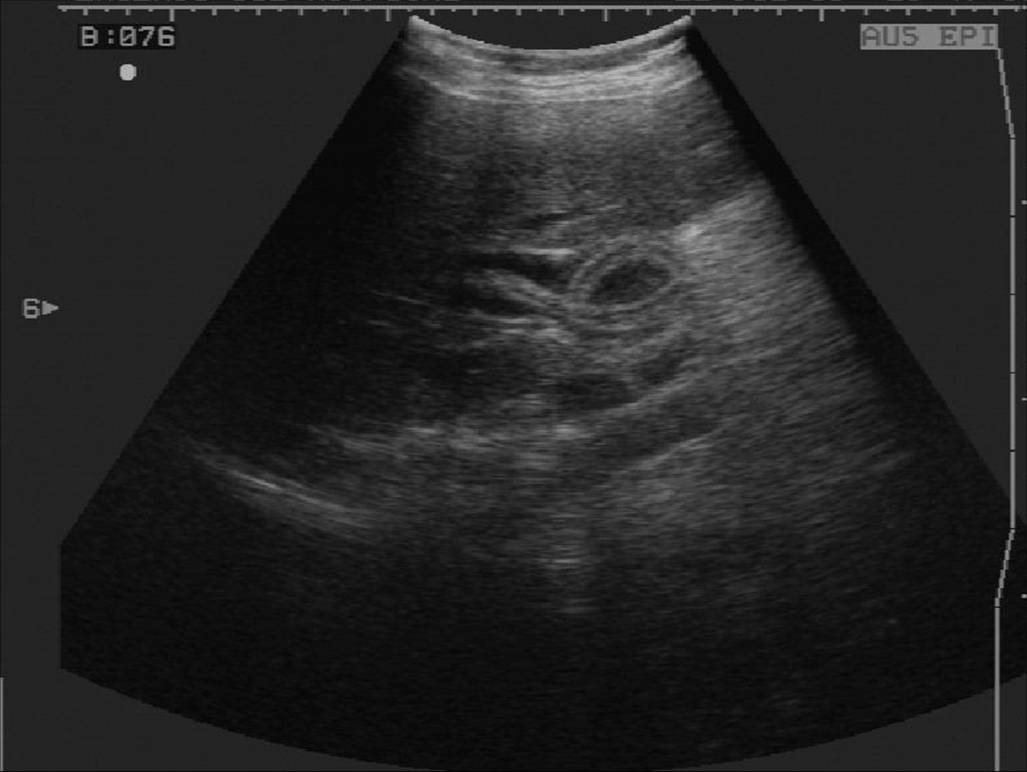

1 胆管结石

2 肝外胆管癌

3 先天性胆管囊状扩张症

4 胆道蛔虫病